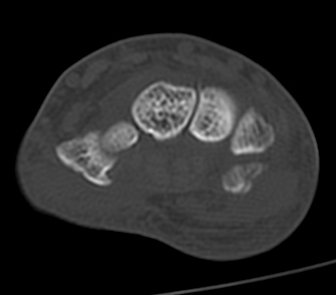

ÃÊÀ½ÆÄ°Ë»ç : ¼Õ¸ñ ¼ö±Ù°ü ±ÙÀ§ºÎ Ⱦ´Ü¸é°Ë»ç¿¡¼­ Äá¾Ë»À Ç¥ÃþÀ¸·Î ¾à°£ÀÇ ¿¬ºÎÁ¶Á÷ ºÎÁ¾ÀÌ °üÂûµÊ(»çÁø 1).